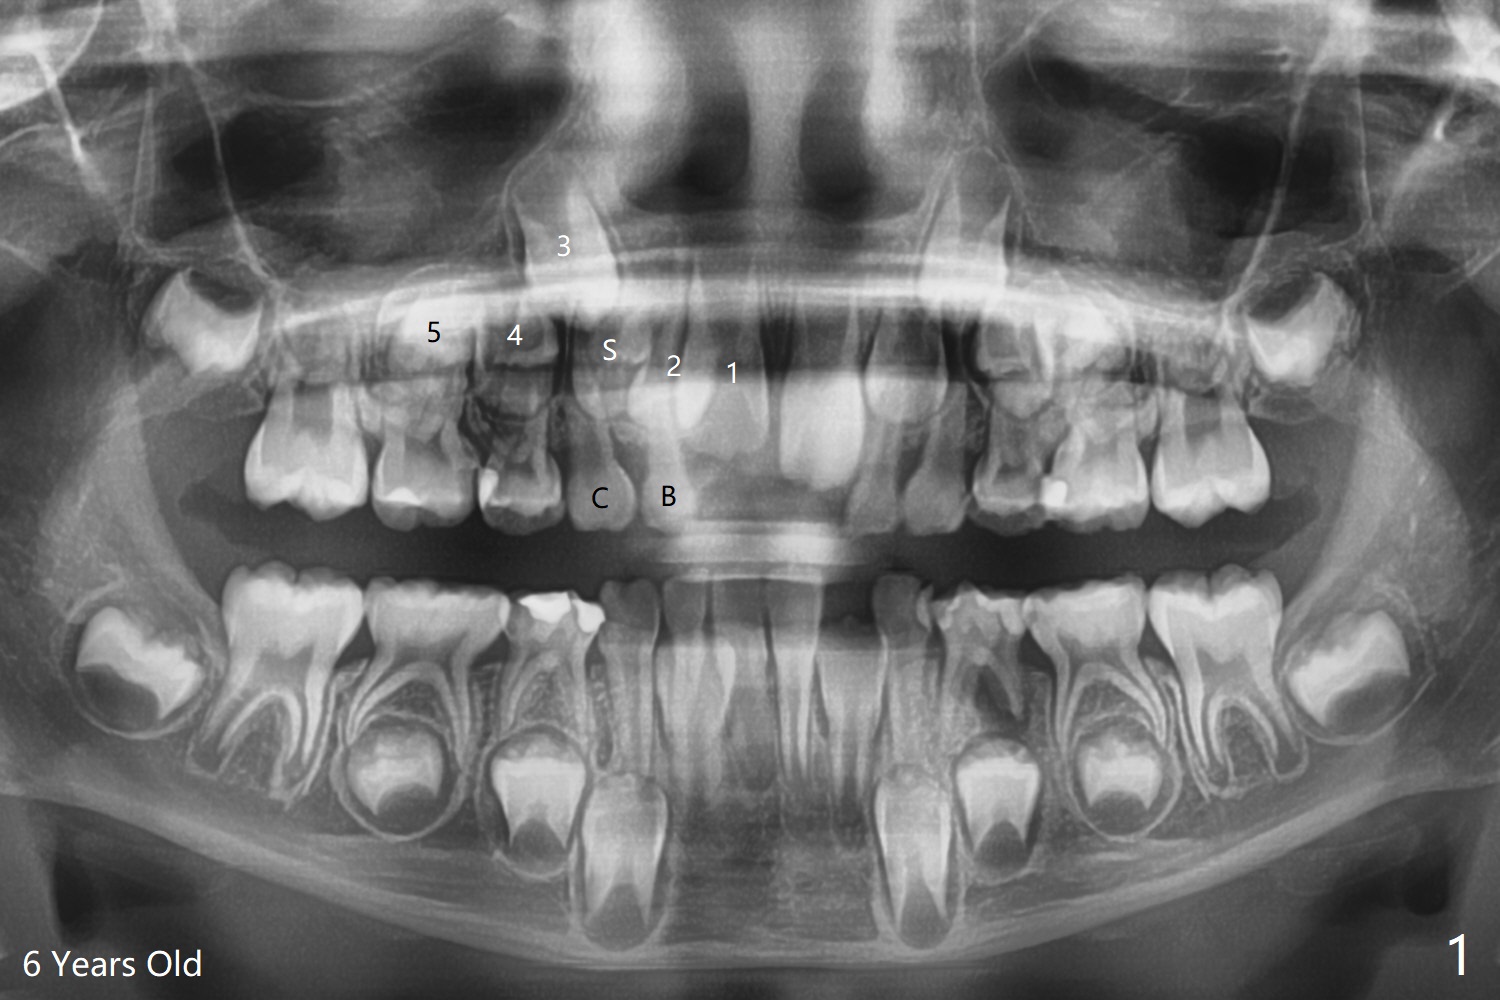

A 6-year-old woman presents to office for limited exam for caries (Fig.1). What was neglected is a super-numerary tooth (S) between UR2 and 3. One year later, the extra tooth appears to be erupting (Fig.2) and linguali-zing UR2 (Fig.3 arrow). PA shows that the extra tooth looks like a lateral (Fig.4). CT will be taken to decide which tooth needs for extrac-tion. The super-numerary tooth (S) blocks UR3 descent, as compared to that of UL3 (Fig.5). The super-numerary tooth with an abnormal cingulum (Fig.6 *) and dens in dente (Fig.6 ^) should be extracted.